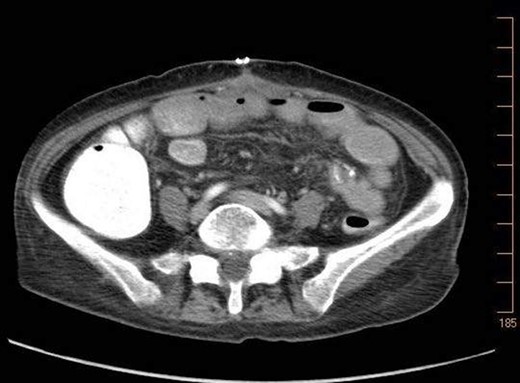

On 7.8.18 the patient had return of bowel function complicated by blood per rectum and an episode of bloody emesis with drop in Hgb 9 > 7.0. The patient received 2 units PRBCs. GI consulted deemed blood per rectum likely from bleeding from anastomoses line. 7.8 Zosyn began for 7 days. Due to the concern for potential bleed, on 7.9 the patient had CTAP (Fig. 5) which demonstrated newly developed pneumatosis within ascending and transverse colon. Pt at this time had appropriate post-surgical abdominal pain, no leukocytosis 4.6, and was HDS. Decision was made to conservatively manage this form of colonic pneumatosis, with TPN, antibiotics, and bowel rest. 7.11 EGD revealed a 5 mm ulcer at duodenal bulb. CTAP (Fig. 6) on 7.14.18 demonstrated largely resolved pneumatosis of ascending and transverse colon. 7.17 Mechanical soft diet, discharged home.

7.14.18: CTAP w/IV and PO contrast: largely resolved pneumatosis.